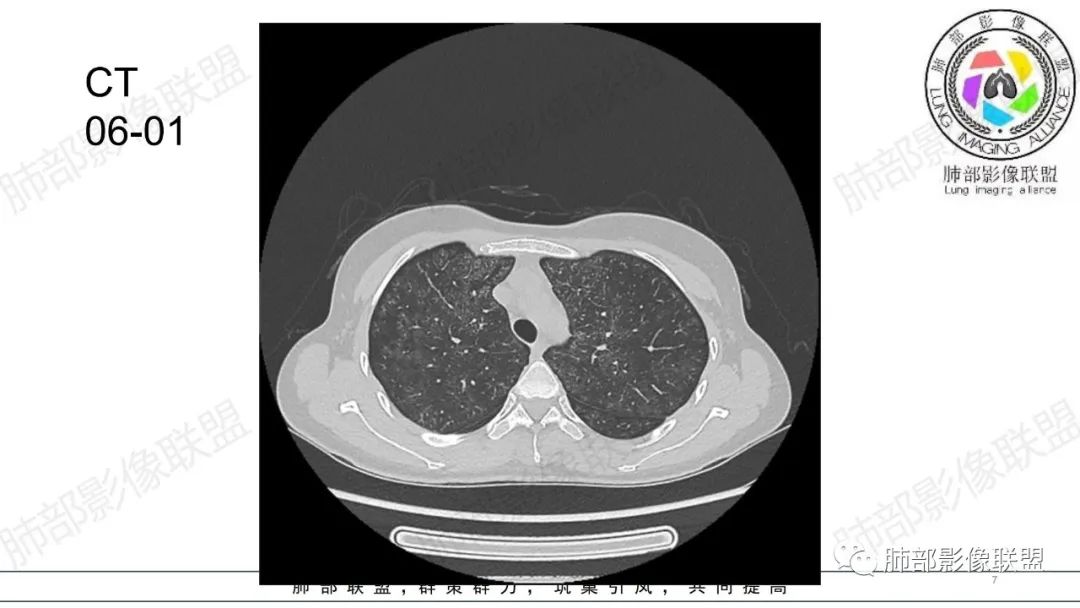

影像资料

34岁女性患者,“哮喘”病史30年,近期有可疑刺激性气体吸入史;因乏力半年,咳嗽、憋气、发热4天就诊;6.1CT提示双肺广泛毛玻璃影及粟粒样结节,胸膜下闲置及血管周闲置,可见树丫征,部分小叶间隔增厚。考虑:1.过敏性肺泡炎,有可疑刺激气体接触史,胸膜下闲置,广泛毛玻璃影,地图样分布,粟粒结节边界模糊,支持过敏性肺泡炎,但糖皮激素治疗效果不佳,且动态复查血常规血红蛋白进行性降低,过敏性肺泡炎 不符合;2.肺含铁血黄素沉积症:患者30“哮喘”病史,可能为肺含铁症状,肺部CT提示双肺弥漫毛玻璃影及粟粒结节影,中下肺明显,肺底部分小叶间隔增厚,近期咳嗽、憋气、发热,血常规血红蛋白进行性下降,考虑肺含铁急性期症状,但临床无咯血症状,肺含铁不典型。综合考虑:肺含铁血黄素沉积症>过敏性肺泡炎。

年轻女性 ,急性喘息发热,肺部影像弥漫磨玻璃密度,部分细小腺泡结节,胸膜下黑线显示,短期复查,病变密度增高,下肺明显,血管周围肺组织累及较少、且逐渐成小叶间隔分布。考虑弥漫肺泡内病变,并经淋巴道转移,下肺比上肺明显,多为免疫细胞功能下肺较强。1.过敏性肺泡炎,有相关病史,三层密度特点、头尾测分布,符合。2 肺泡微石症,多有钙化,且缓慢起病,病程不太符合,放待排。3 吸入相关肺损伤,有病史,疾病演变过程也符合渗出-肉芽肿改变,建议详细询问病史。4 感染性病变,结核?病变气道分布为主,如此弥漫且没有树丫不符合。5.巨细胞病毒,可以磨玻璃 结节 改变,没有免疫缺陷病史。最后考虑吸入所致 1过敏性肺泡炎、吸入性肺损伤 鉴别肺泡微石症。